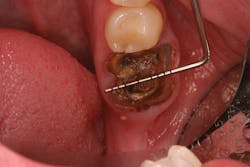

Because of this alveolar resorptive pattern after tooth extraction, bone grafting the extraction socket after tooth extraction procedures has become a solution that attempts to limit the amount of hard- and soft-tissue loss. There are many systematic reviews in the literature that compare the results of residual ridge dimension following tooth extraction after the use of a bone graft (with or without a membrane) versus extraction alone without grafting.7

Indications for bone grafting extraction sites include:

• site development to increase hard and soft tissue for pontic sites in fixed bridge prosthetics (figures 9–14);• correcting bone defects impinging upon anatomical structures after tooth extraction, such as oroantral communication (figure 18); and

• preserving tissue structure for subsequent dental implant therapy.Decision matrix